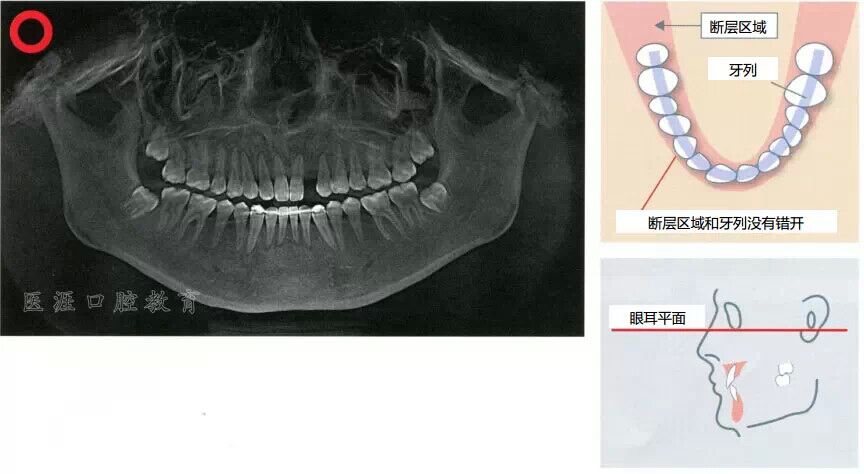

全景X光片

斷層區(qū)和牙列吻合的時(shí)候